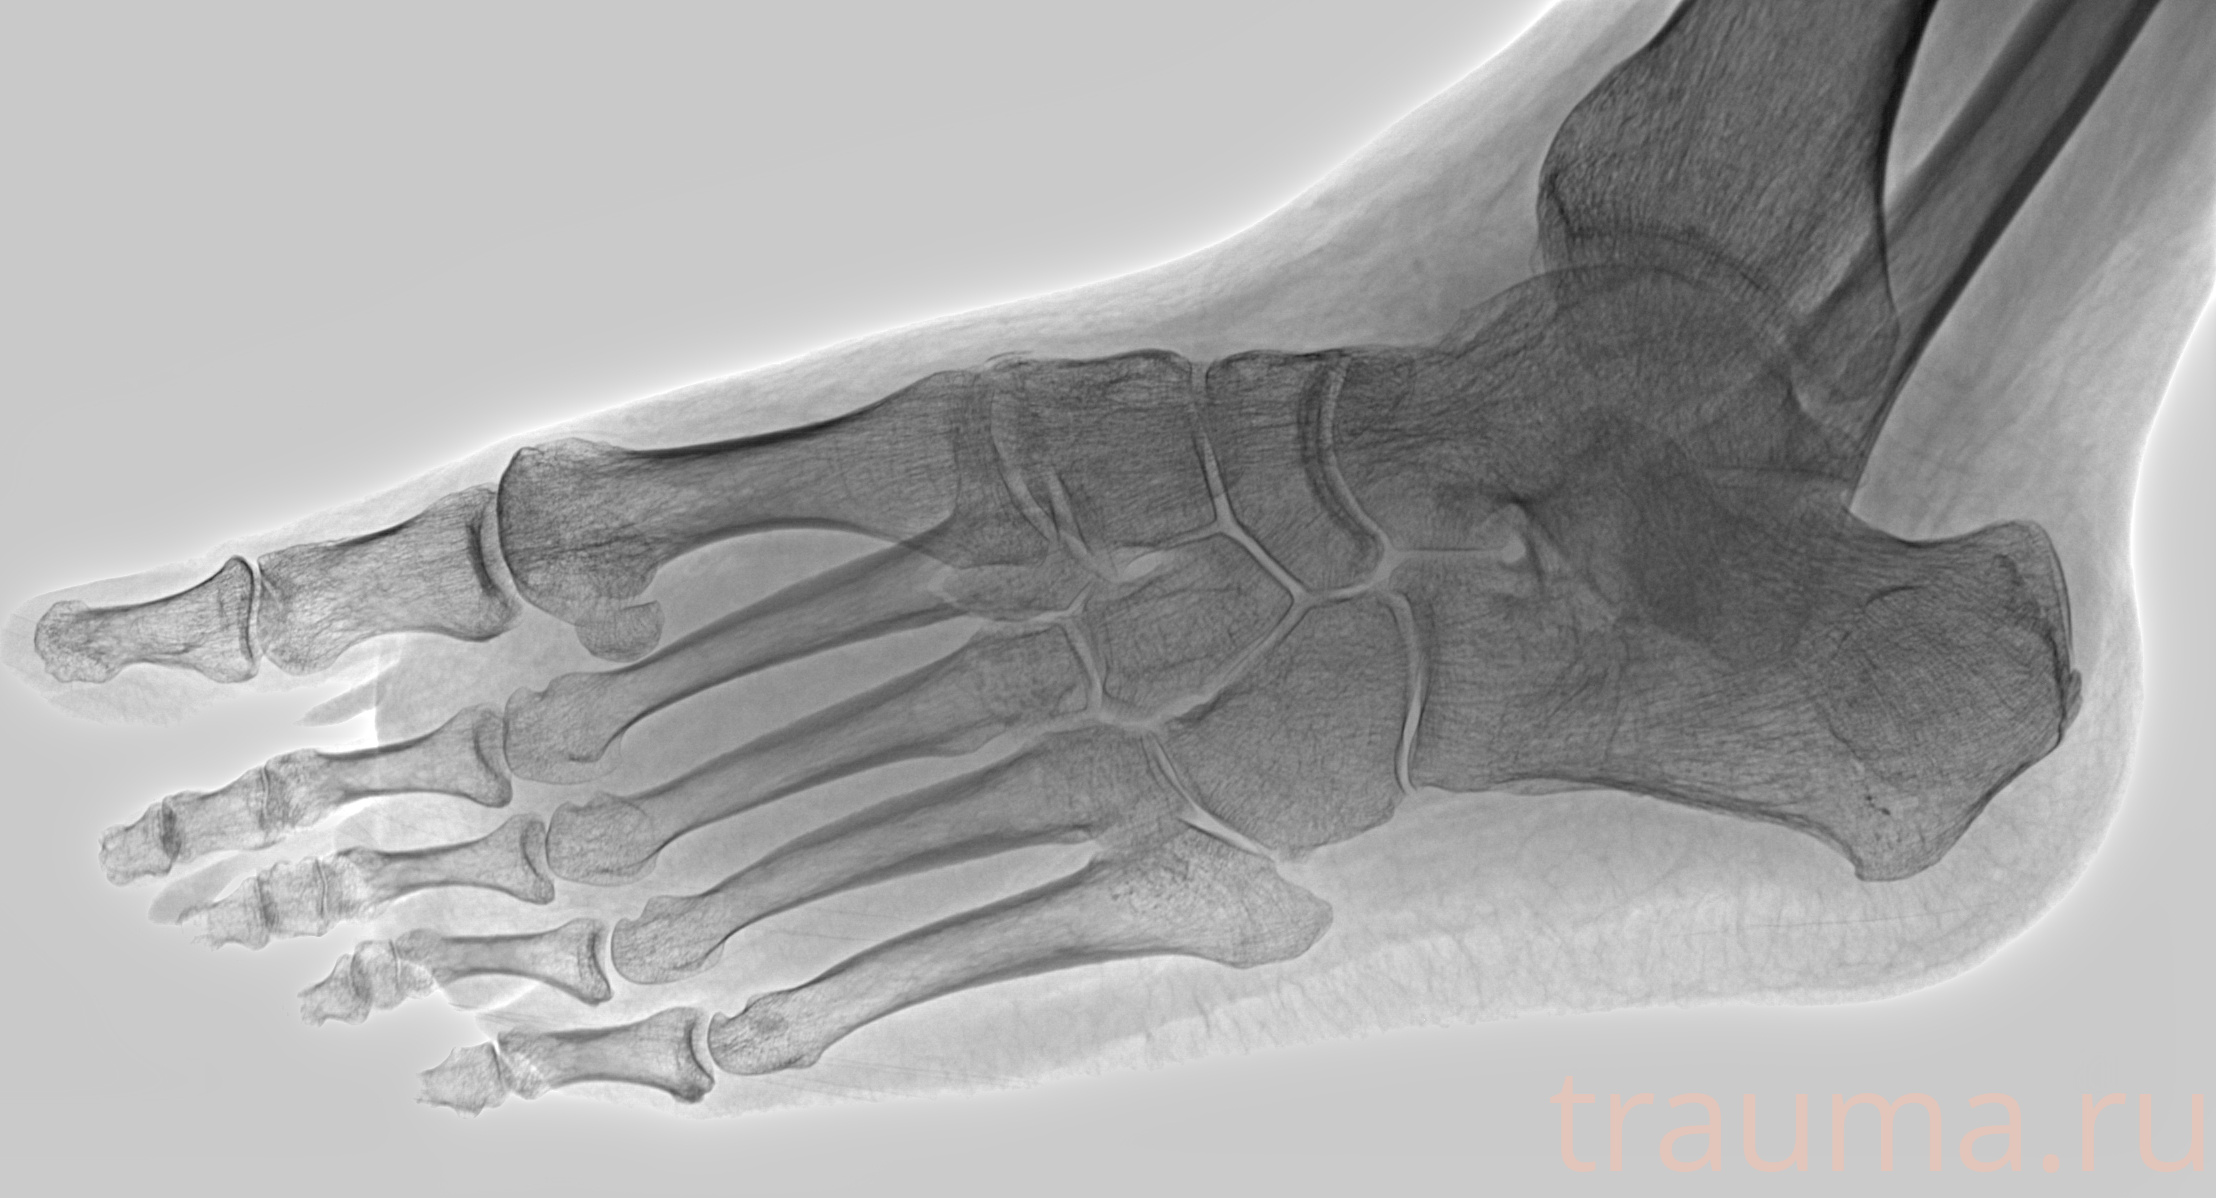

Рентген на дому: по вашему адресу приезжает врач-рентгенолог, травматолог-ортопед с мобильным рентгеновским аппаратом, проводит диагностику травмы или заболевания, делает необходимые рентгенограммы, дает рекомендации по дальнейшему лечению. Получить качественные снимки в домашних условиях возможно благодаря уникальной методике, разработанной МосРентген Центром для института  Склифосовского